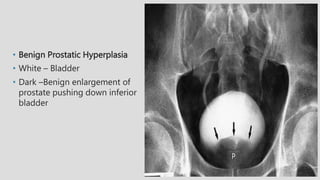

• Benign Prostatic Hyperplasia

• White – Bladder

• Dark –Benign enlargement of

prostate pushing down inferior

bladder